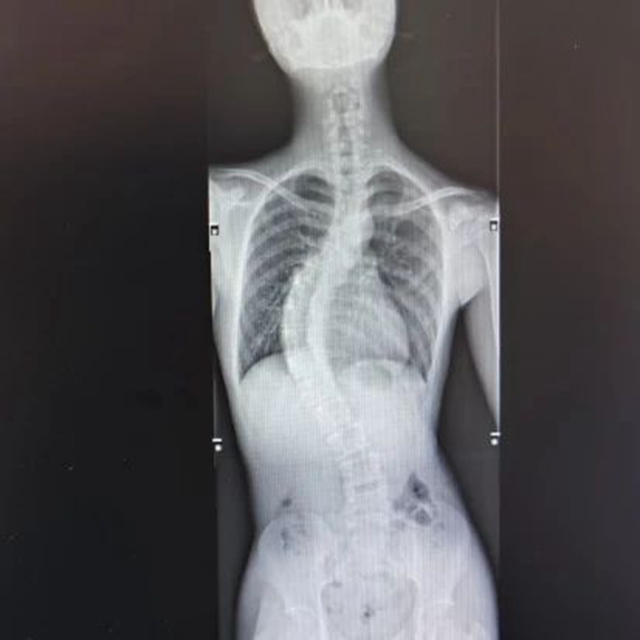

术前影像

脊柱里是脊髓和神经,不耐受牵拉,更不能损伤,小黄的脊柱侧弯严重,达到了63度,手术难度高、创伤大、时间长、风险高。为了最大程度确保手术安全,科室副主任杨杰翔副教授组织了全科讨论,制定了详细的手术方案。